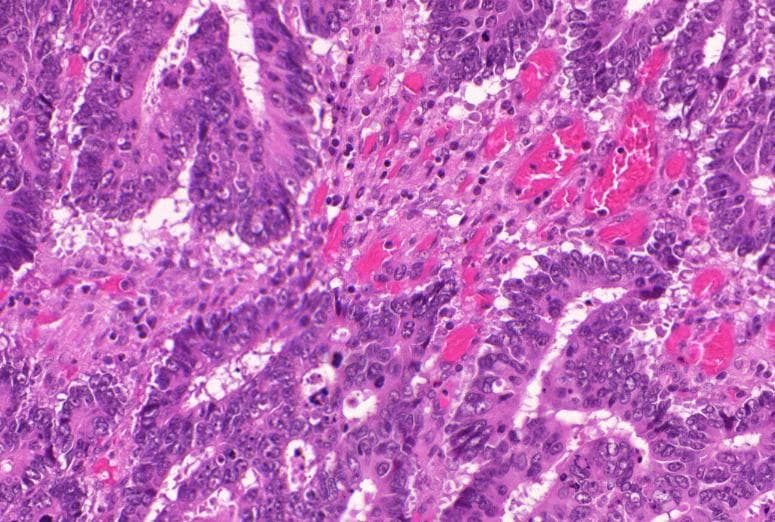

Tumor cells infiltrate in acinar and papillary patterns with irregular lumina, partially in back-to-back arrangement. Nuclei are hyperchromatic and variably sized with visible nucleoli and eosinophilic cytoplasm. Stromal fibrosis present without keratin pearl formation or perivascular cuffing. Cell adhesion preserved with some desquamation.

Significantly enlarged and hyperchromatic nuclei with increased nuclear-to-cytoplasmic ratio, irregular nuclear membranes, and nuclear crowding suggest high-grade atypia consistent with typical cancer cell cytology — a key region for tumor characterization.

Under high magnification, tumor cell nuclei are significantly enlarged and hyperchromatic with clearly visible nucleoli. Intracytoplasmic mucin vacuoles of varying sizes suggest adenocarcinoma features. No intercellular bridges or keratinization observed.